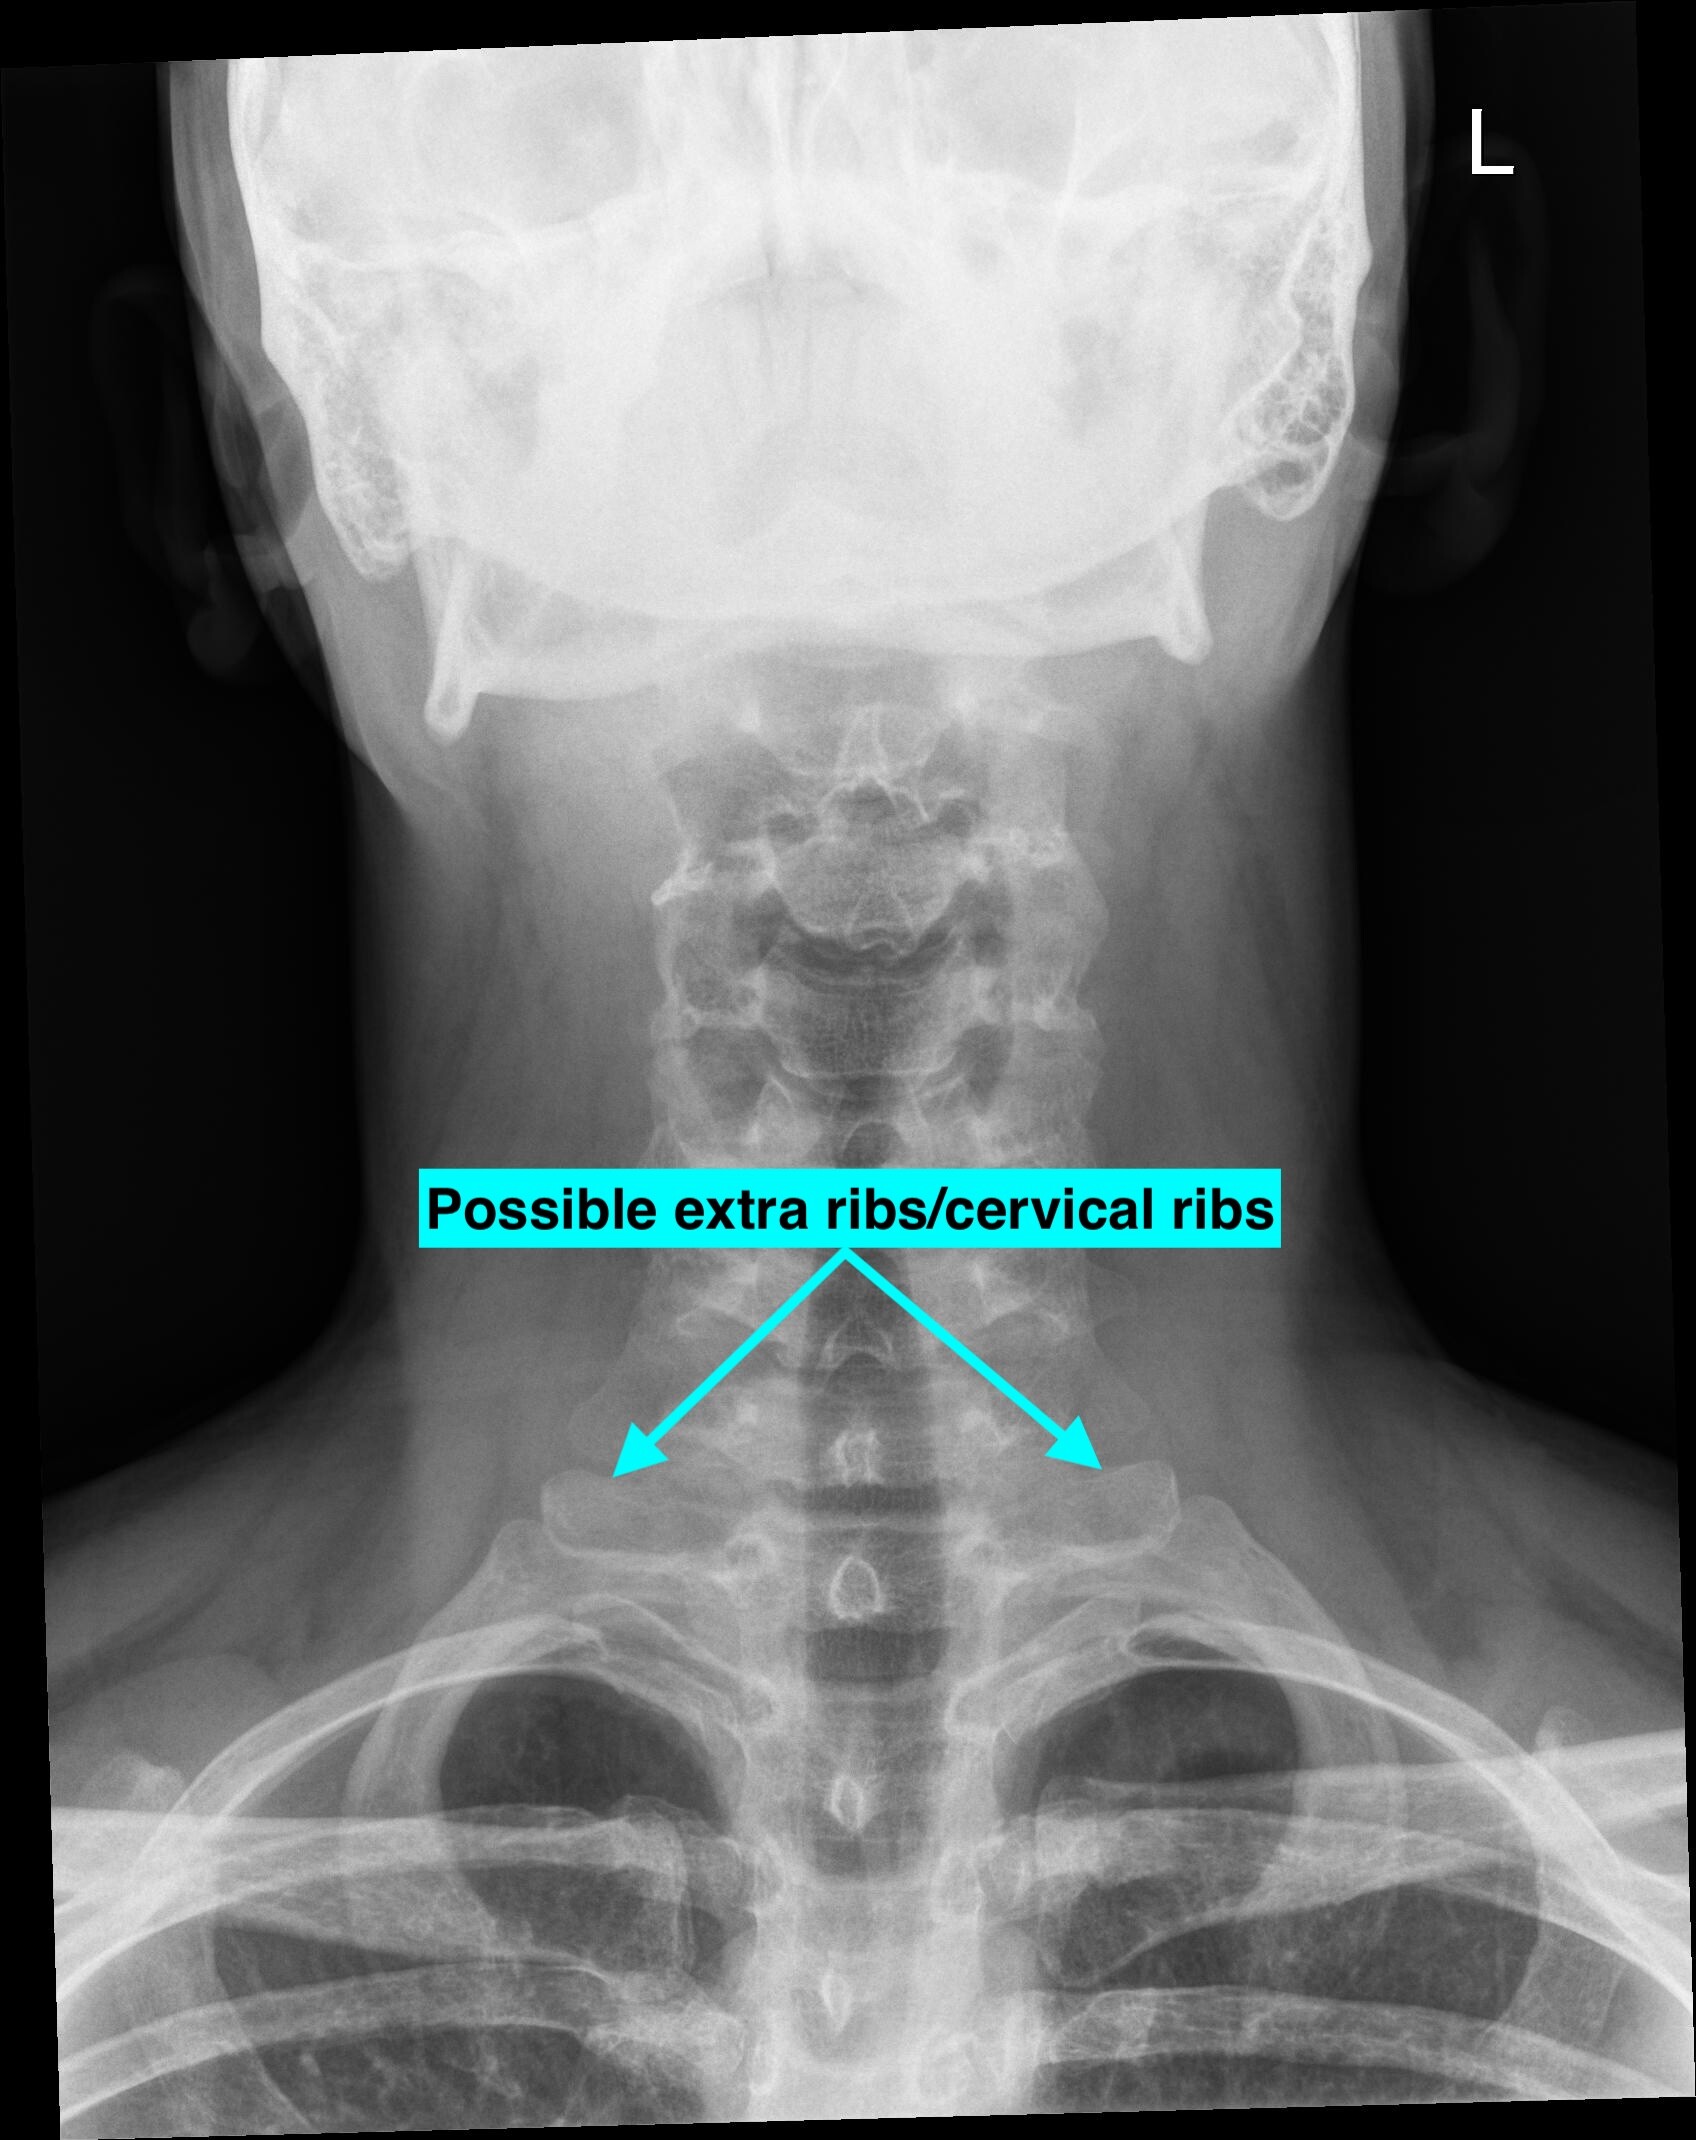

The last image looks like you may have cervical ribs. (extra set of ribs). They can cause thoracic outlet syndrome with similar symptoms as ES. Need a chest x-ray to see all your ribs to be sure.

I annotated a couple of the images to show you what I’m guessing might be abnormal. You must remember we aren’t doctors so nothing we tell you can be used for an official diagnosis.

@Eazy You can have both ES and TOS with cervical ribs. In the image above it looks like a classic image of someone with cervical ribs. Need to verify with image to count all ribs just as you need to verify styloids with CT. Its not uncommon to have multiple spot of venous compression. Treating one may not help. Not knowing what your dealing with before treating one can lead to problems. Just trying to be helpful. Again I’m not a MD and just taking a educated guess.